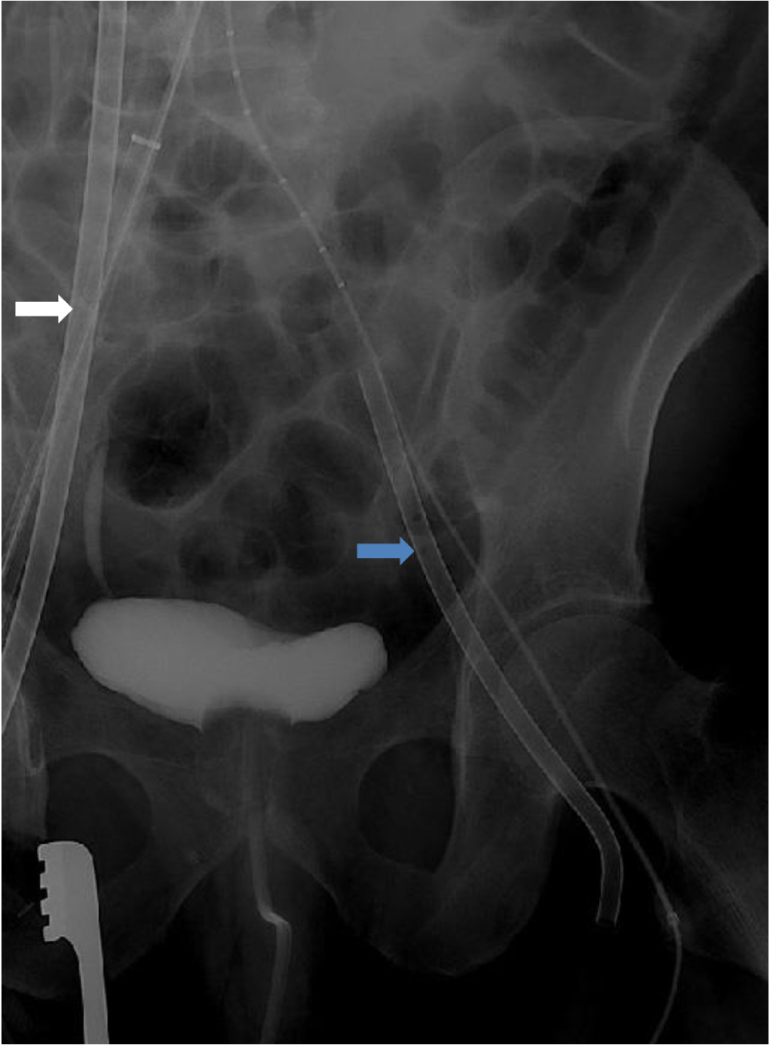

A 40-year-old male (140kg, 165cm) patient was transferred to our emergency room with chest pain. He had hypertension, coronary artery disease, and bronchial asthma that were not treated. He visited the pulmonology department with exertional dyspnea one year before surgery. On pulmonary function test, he had mild obstructive airway disease and allergen skin prick test revealed bronchial asthma to specific allergen. On chest X-ray, there was no abnormal finding (Figure 1). Contrast-enhanced computed tomography scan revealed Stanford type B aortic dissection from descending thoracic aorta to iliac arteries (Figure 2). Despite medical treatment with labetalol (120mg/h) and nicardipine (2.5mg/h), lower limb ischaemia and acute renal failure developed due to malperfusion at HAD #2 (Figure 3). Urgent surgical intervention was needed. Thoracic endovascular aortic repair (TEVAR) followed. Before transferring him to the operating room, 0.2mg glycopyrrolate was injected intramuscularly. For anaesthetic induction, 2% propofol and remifentanyl were used. The patient was paralyzed with 50mg rocuronium. Anaesthesiologist had a difficult time in endotracheal intubation with poor laryngoscopic view. After endotracheal intubation, expiratory tidal volume was 100ml with high inspiratory airway pressure (70cmH2O). On arterial blood gas analysis after 100% oxygen inhalation, severe hypoxemia and respiratory acidosis were found (pH 7.198, PCO2 61.8mmHg, PaO2 26.4mmHg, O2 Saturation 36.1%). The anaesthesiologist performed flexible bronchoscopy. There was no endotracheal or endobronchial obstruction. Severe bronchospastic asphyxia was suspected and epinephrine 0.5 mg was given subcutaneously. Then 0.5ml albuterol of 0.5% formulation was inhaled into the endotracheal tube. Methylprednisolone (1mg/Kg) was also given intravenously. After conventional therapy for severe bronchospasm, his hypoxemia and respiratory acidosis were slightly improved (pH 7.264, PCO2 56.7mmHg, PaO2 43.2mmHg, O2 Saturation 71.3%). However, his blood pressure dropped down (systolic blood pressure<70mmHg) and bradycardia (40/min) developed. Conventional therapy was ineffective for him and cardiac arrest caused by persistent hypoxemia was impending. At 12 minutes after bronchospastic attack, emergent venovenous extracorporeal life support (VV ECLS) was initiated. A 21 French drainage cannula (Bio-Medicus™ Multi-Stage Femoral Venous Cannula, Medtronic, Minneapolis, MN, USA) was inserted into the right common femoral vein and advanced into right atrium. A 17 French return cannula (Bio-Medicus™Femoral Arterial Cannula, Medtronic, Minneapolis, MN, USA) was placed at the left external iliac vein. The anaesthesiologist already inserted central venous catheter into the right internal jugular vein. Only both groins were cleansed and draped for TEVAR. Therefore, we planned secondary cannulation via the right internal jugular vein if needed after emergency VV ECLS via femoral venous cannulation. All procedures were done percutaneously with fluoroscopic guidance (Figure 4). Quadrox oxygenator and rotaflow pump (Maquet, Hirrlingen, Germany) were connected to extracorporeal circuit. Extracorporeal circulatory blood flow rate was 4.5L/min. Peripheral O2 saturation raised up to 80%. He was stabilized haemodynamically. We changed the mode of mechanical ventilation from volume controlled to pressure controlled ventilation. Limitation of inspiratory airway pressure was 40cmH2O. Expiratory tidal volume was less than 70ml. After VV ECLS, hypoxemia and hypercarbia were improved on arterial blood gas analysis (pH 7.305, PCO2 49.6mmHg, PaO2 56.2 mmHg, O2 Saturation 86.2%). Intimal tearing portion of thoracic aorta was sealed with stent graft (Valiant thoracic stent graft with the Captiva delivery system, Medtronic) on VV ECLS. The patient was transferred to intensive care unit after surgery without any problem. Bronchodilator was used for inhalation every 4 hours. After 12 hours after VV ECLS, his expiratory tidal volume was increased up to 450ml with appropriate inspiratory airway pressure (less than 40cmH2O). VV ECLS was weaned at POD#1 and decannulation was done without haemorrhagic complication. Patient could be weaned from mechanical ventilator and extubated at POD#2. He could be discharged at POD#7 without any respiratory or cognitive dysfunction. Malperfusions of left kidney and left iliac artery were resolved and there was no abnormal finding of lung parenchyma and pulmonary vessels on contrast-enhanced computed tomography scan at POD#14 (Figure 5). The patient has been treated with a bronchodilator at the Pulmonology Department. He has no more episode of bronchospastic asphyxia.

Contrast-enhanced computed tomography scan showing malperfusions of left kidney (white arrow) and left iliac artery (blue arrow)

Venous cannulations for extracorporeal life support under fluoroscopic guidance. A 21 French venous cannula was inserted into the right common femoral vein for venous drainage (white arrow). A 17 French arterial cannula was inserted into the left common femoral vein for return (blue arrow).